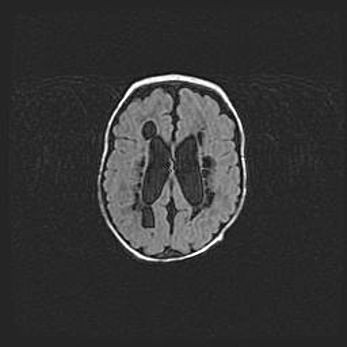

Сообщающаяся гидроцефалия. Кистозная энцефаломаляция головного мозга.

Возраст: 3 месяца 4 дня

Вес: 3100 г

Пол: женский

Окружность головы: 34 см

Срок гестации: 31 неделя

Кистозная энцефаломаляция головного мозга - одна из форм поражения головного мозга в детском возрасте. Характеризуется возникновением множественных и распространённых кист в коре, белом веществе и подкорковых образованиях головного мозга у плодов, новорождённых и детей раннего возраста. Развитие кистозной энцефаломаляции связано с внутриутробной асфиксией и гипотонией, родовой травмой, тромбозом синусов, пороками развития сосудов, инфекциями, сепсисом и другими причинами. Наиболее значимые инфекционные агенты: вирусы простого герпеса, цитомегалии, краснухи, токсоплазмы, энтеробактерии, золотистый стафилококк и другие.